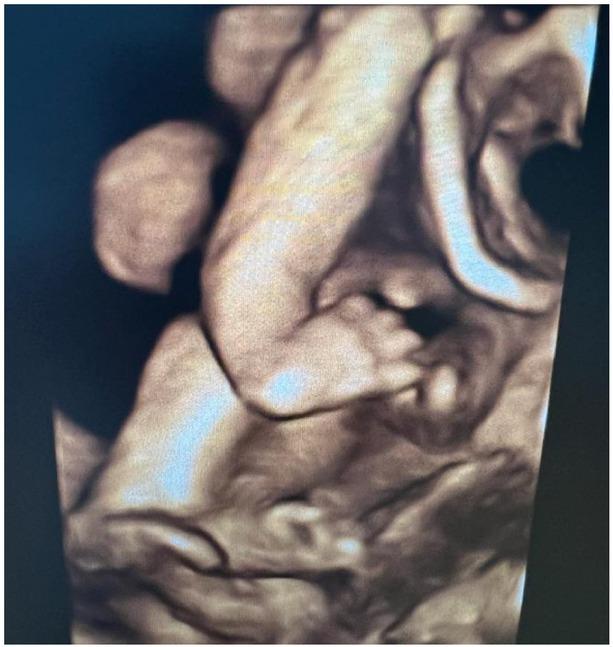

超声检查用于评估产前筛查中的异常发现。桡骨射线缺陷可通过超声检查进行筛查。通过了解病因、病理生理学和胚胎学,可快速检测到异常发现。这是一种罕见的先天性缺陷,可能是孤立的,也可能与其他异常有关,包括范可尼综合征和霍尔特-奥拉姆综合征。我们报告一例28岁女性(G2P1L1)的病例,根据末次月经日期,该患者在孕25周0天时前来进行常规产前超声检查。该患者未进行任何二级产前异常扫描。进行了超声检查,根据超声扫描确定的孕周为24周3天。在本文中,我们简要回顾了胚胎学和关键实践要点,并报告了一例罕见的伴有室间隔缺损的桡骨射线综合征病例。

Prenatal 2D and 3D ultrasound diagnosis of radial ray defects.产前二维和三维超声诊断桡骨射线缺陷。

Int J Gynaecol Obstet. 2011 May;113(2):158-9. doi: 10.1016/j.ijgo.2010.12.009. Epub 2011 Mar 22.